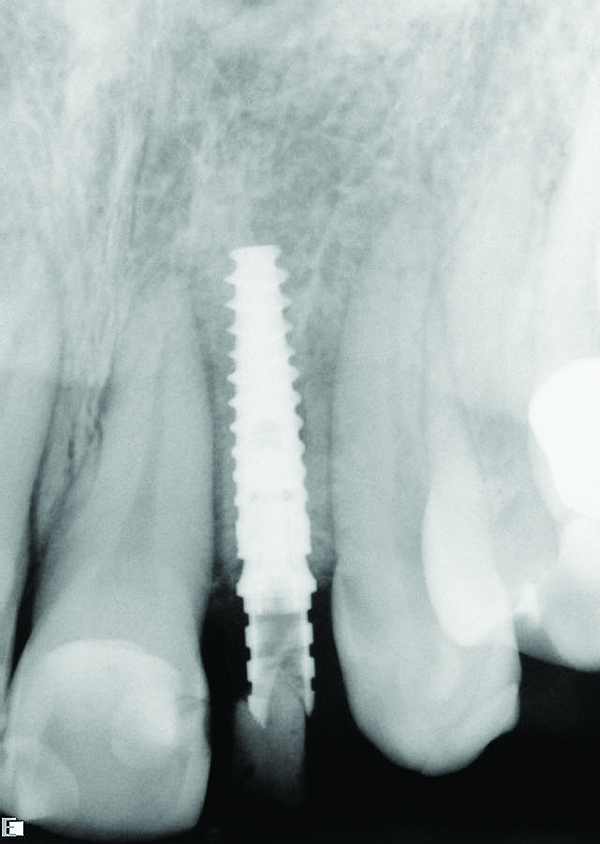

Fig 9. Radiograph taken at the time of implant placement confirming that the implant is precisely positioned, matching the presurgical plan.

Figure 9